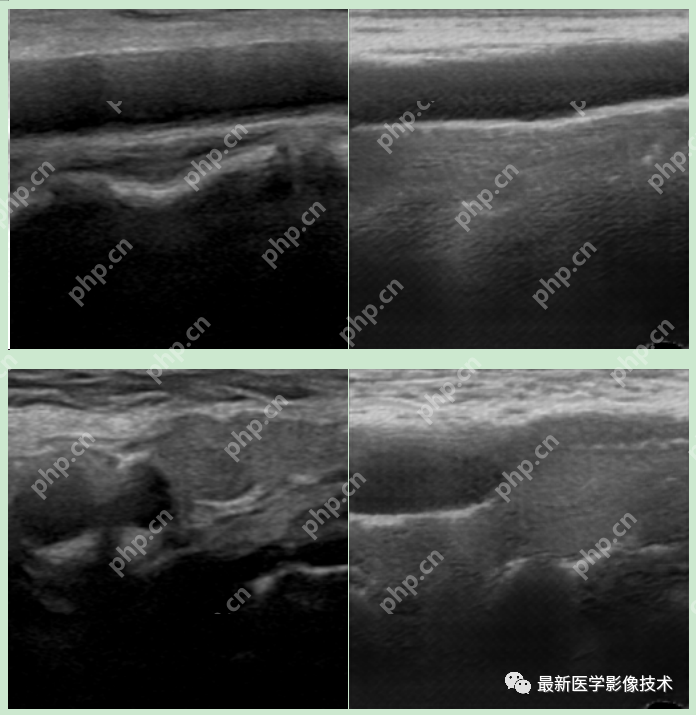

5、验证集部分生成结果

左图为低质量图像,中间为生成的高质量图像,右图为真实的高质量图像。